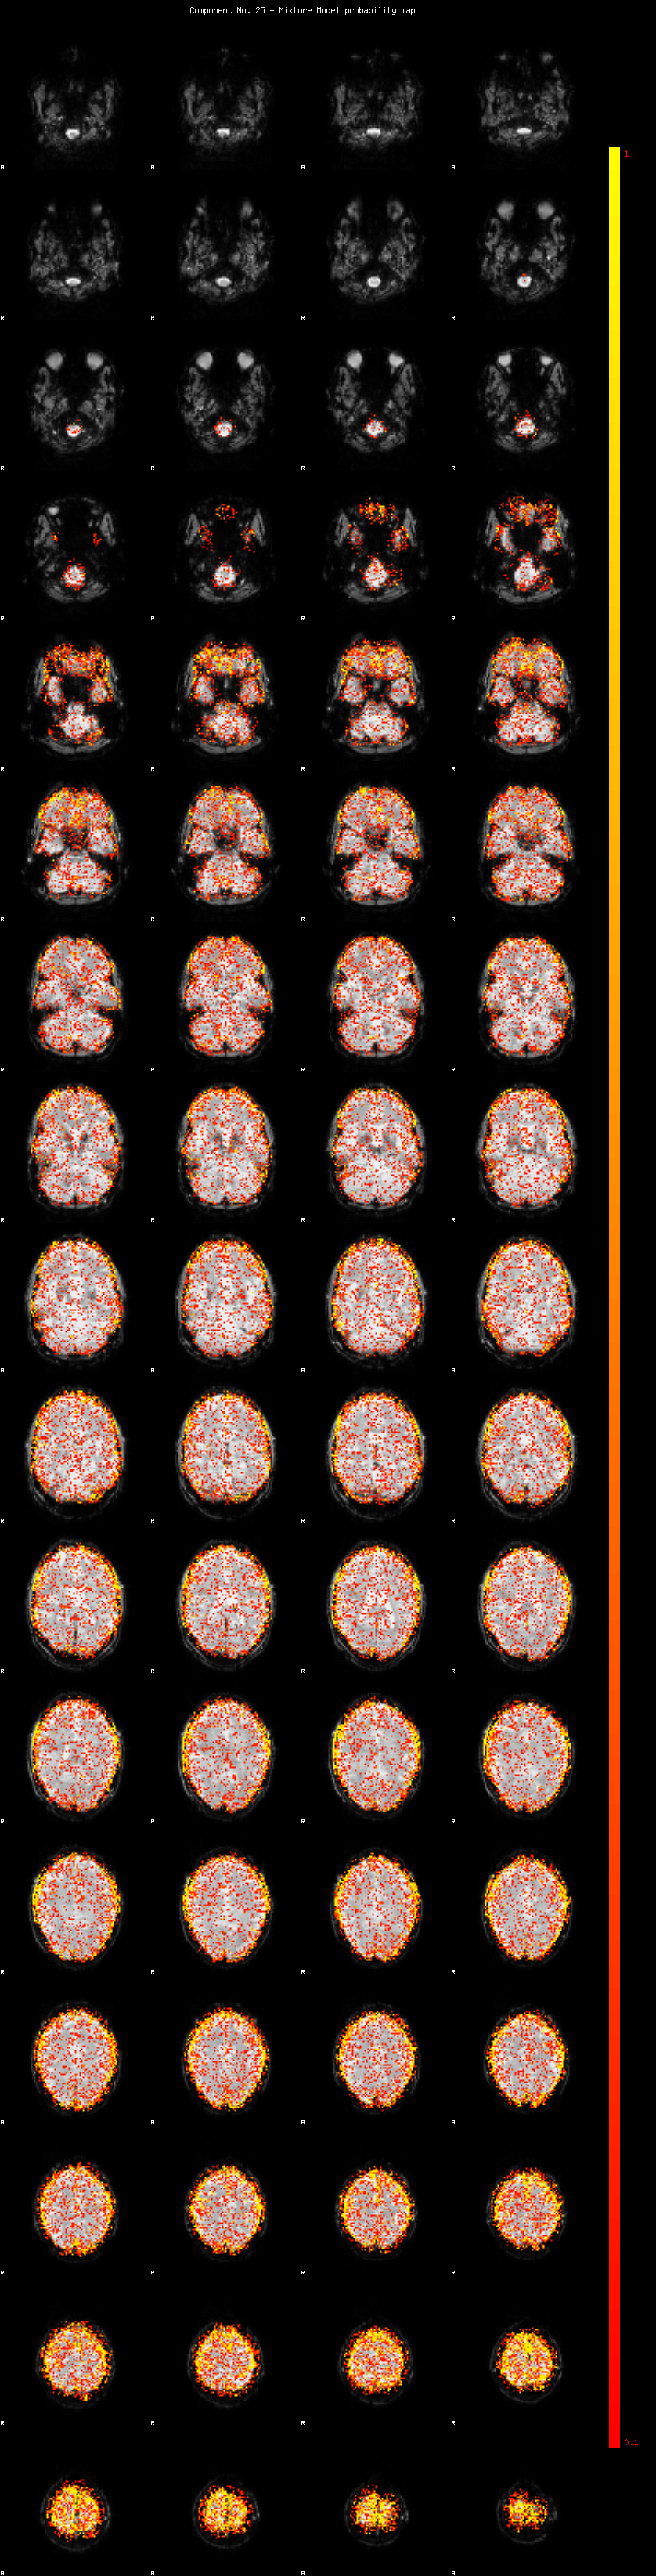

IC_25 Mixture Model fit

Means : 0.000000 2.807051 -2.562412

Vars : 1.000000 2.912548 2.151797

Prop. : 0.856403 0.080330 0.063267